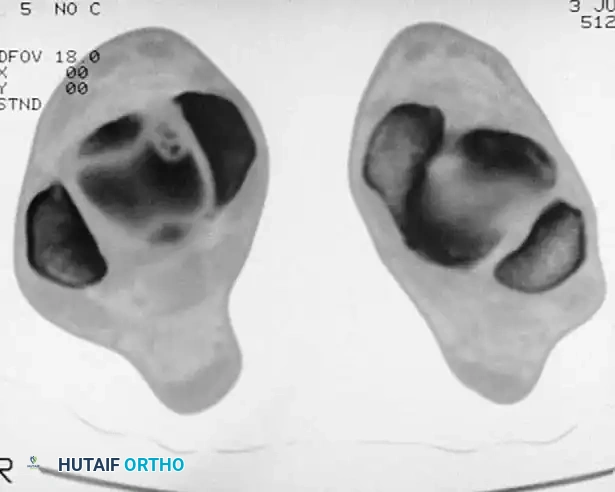

Standard radiographs often fail to accurately locate the lesion's anterior-to-posterior position. Computed Tomography (CT) in the coronal and axial planes is the gold standard for defining the exact location, size, and depth of the crater, which is critical for planning the surgical approach.

High-resolution coronal CT demonstrating a deep medial osteochondral defect requiring surgical intervention.